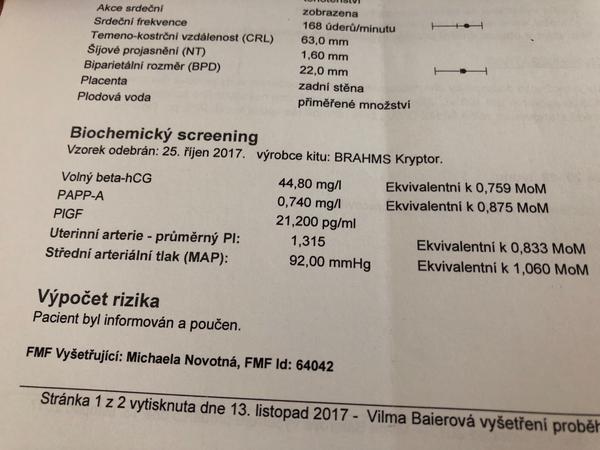

@beruska125 hmm, já mám doporučeno, kvůli nižšímu papp-a, bude se to integrovat do výsledků krve z NT, co jsem teda tak pochopila... dneska se u dr. zeptám víc

@seveneye ano mám to asi ze stejného důvodu, trochu horší výsledky krve u screeningu, ultrazvuk vše v pořadku...

@jednaholkaa Tady jsem schválně našla ty výsledky z předchozích těhotenství 🙂 Obě to jsou holky 🙂 A hodnoty nízké 🙂 Teď zatím hodnoty nevím, na screening jdu ve čtvrtek :D